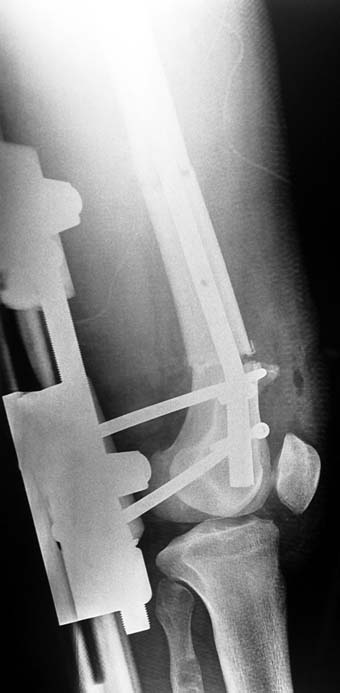

Bu Bacak Kısalık tipi bir kırığın kısalmış pozisyonda kaynaması ile oluşur. Bir çok vaka yetişkinlerde görülür ve sadece bir uzatma ile tedavi edilebilir. Ek deformiteler de aynı anda düzeltilebilir. Bu hastaların çoğu çivi üzerinden uzatma veya tam implante edilen çivi ile tedavi edilebilirler.